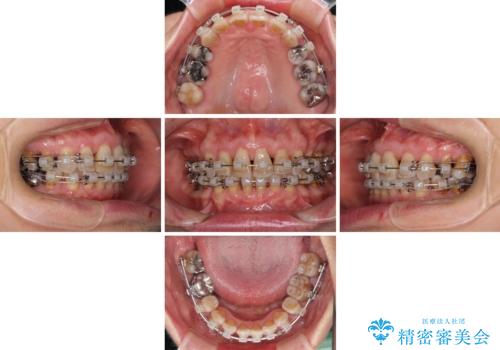

- 矯正装置

- 審美装置

- 治療期間

- 2年10ヶ月

- 治療回数

- 10-30回